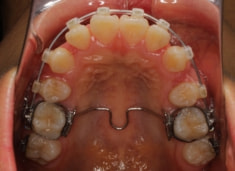

治療開始から11ヶ月後